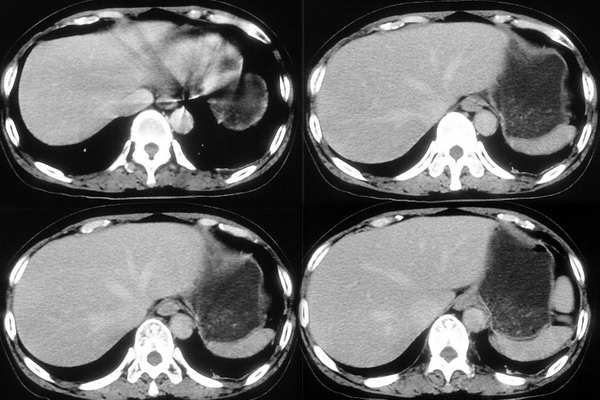

[br]请问战友,肝左叶低密度影和增强后杂乱无章的血管是什么?这是正常的吗?

以下是引用向医生在2005-11-3 21:54:00的发言:[br][br] 我觉得这例除了胆囊结石可以肯定外,肝左叶低密度区考虑为病灶尚不可靠。[br] 在b超下,早期肝脓肿者肝内见较强回声,界限欠清、模糊、形态不规则,如果有坏死液化才会出现低回声,而本例超声下已见低回声,如果真是这种情况的话就是说明病灶内已有坏死液化,这些液化区在ct增强下应该表现为低密度影,本例增强并无这样改变,所以b超的结果可不可靠值得怀疑。[br] 胆囊结石合并胆囊炎也可出现畏寒、发热及白细胞增高等,抗炎治疗后也可症状缓解,不一定非要用肝脓疡来解释。